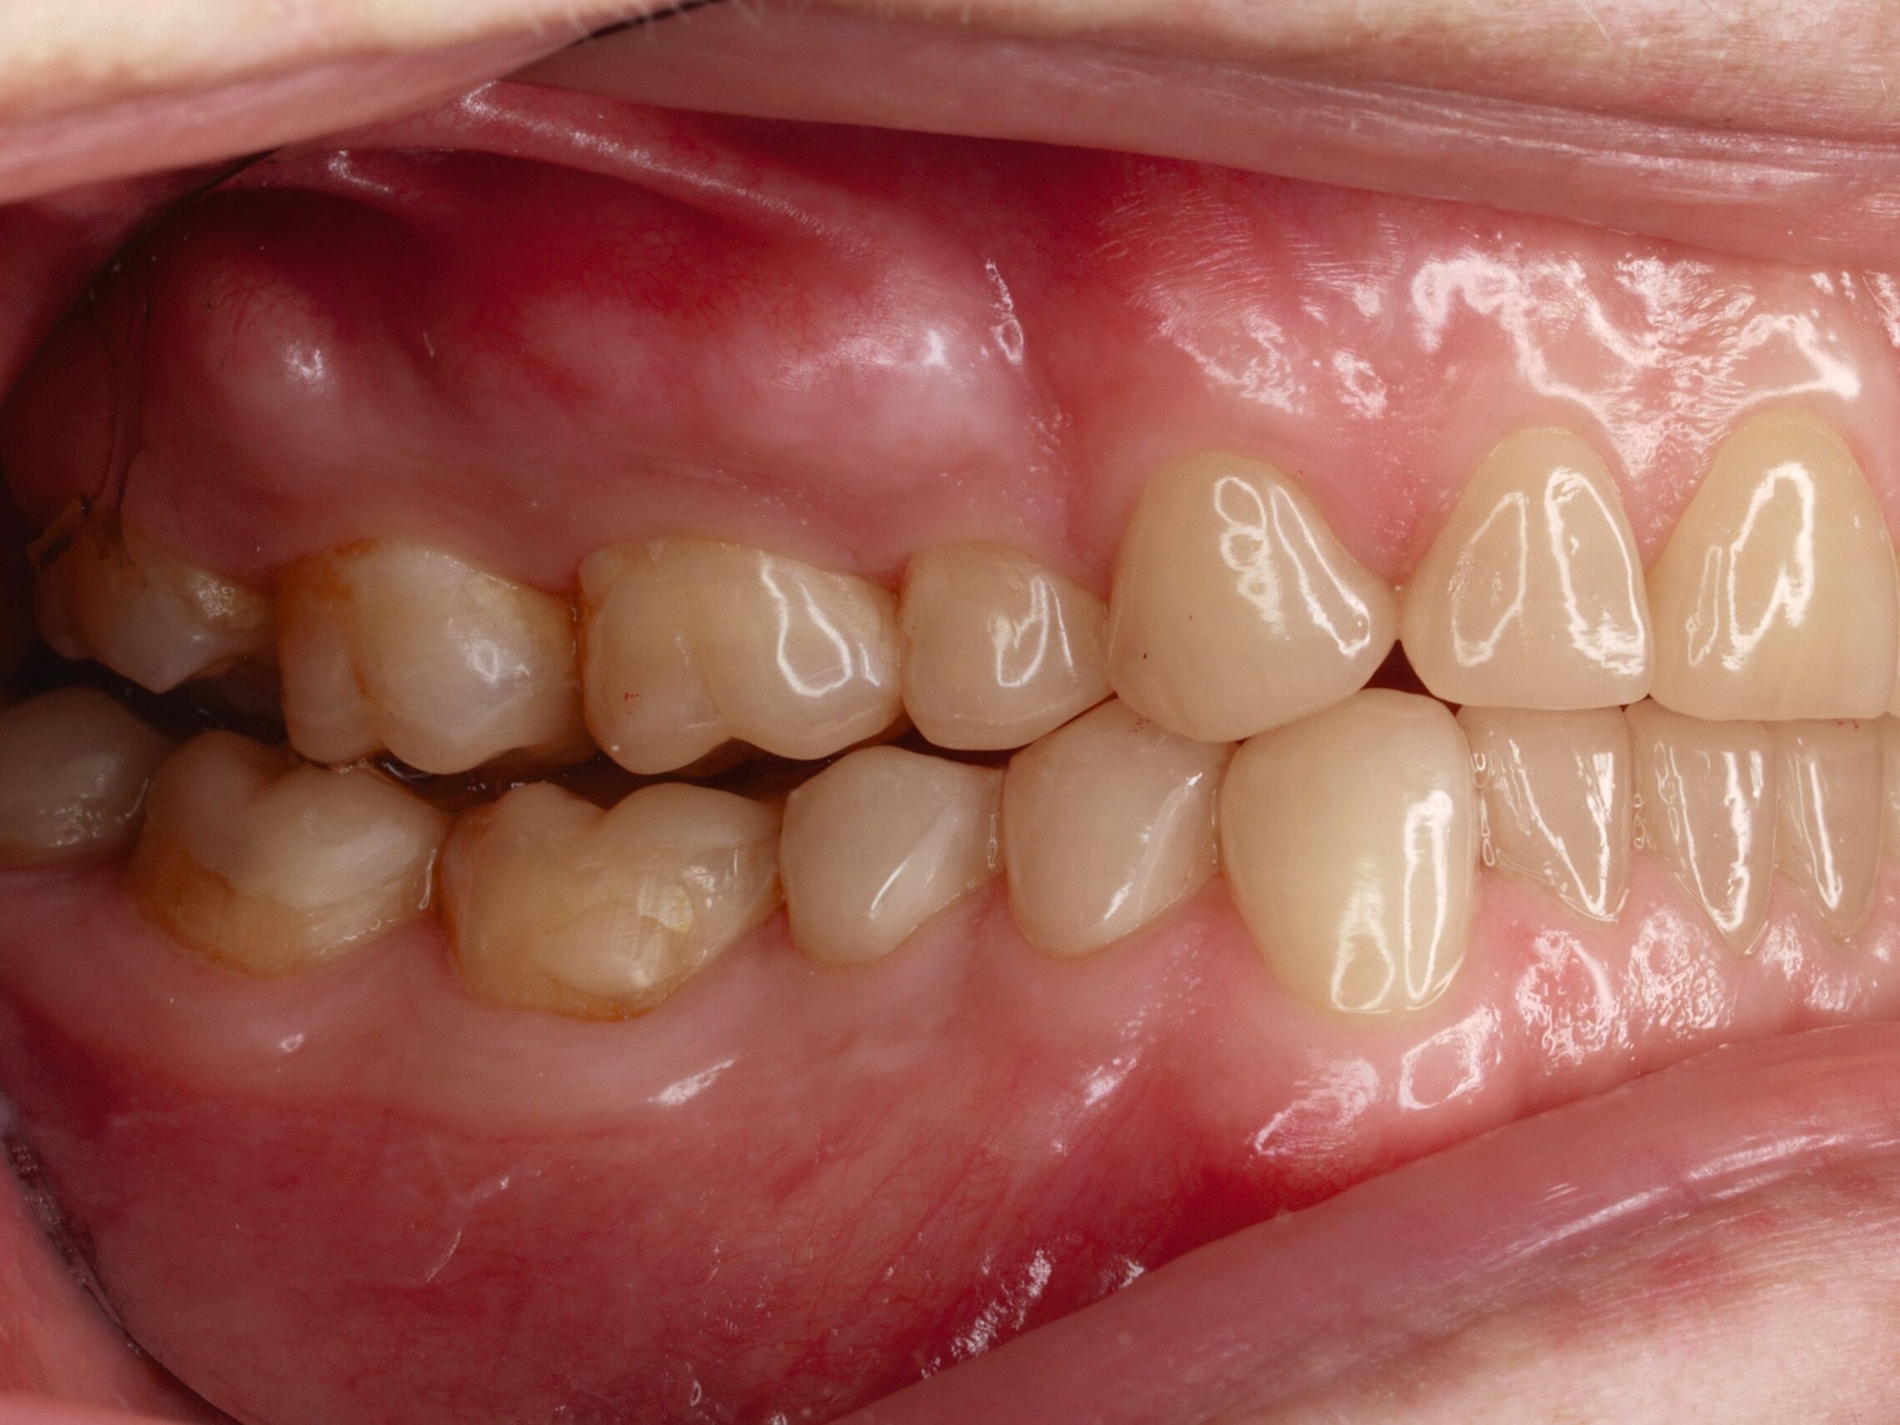

Das unter Beteiligung des Autors entwickelte Tooth Wear Evaluation System (TWES) 2.0 [Wetselaar et al., 2020] identifiziert per Screening Patienten mit erhöhten Verschleißwerten, vergleichbar mit dem PSI in der Parodontologie oder dem CMD-Kurzbefund. Bei auffälligen Werten folgt ein differenzierter Zahnverschleiß-Status einschließlich der Erfassung oraler und vestibulärer Substanzverluste [Wetselaar et al., 2016 sowie von Pathologie-Symptomen und einer strukturierten Diagnose [Tonetti und Sanz, 2019; Wetselaar, 2020]. Den Einsatz in der Praxis illustriert der in den Abbildungen beschriebene Patientenfall aus dem CMD-Centrum Hamburg-Eppendorf.

Im Unterschied zum Zahnverschleiß-Screening wertet der Zahnverschleiß-Status den höchsten Verschleißgrad pro Zahn aus, und zwar okklusal/inzisal, oral und vestibulär (Abbildungen 4b und 4c, Tabelle 1). Wichtig für die Planung therapeutischer Maßnahmen ist die Frage, welche Zähne okklusal in Kontakt stehen, denn die Behandlung von Zähnen mit erheblichem Zahnverschleiß lässt keinen weiteren Substanzverlust zu und erfordert bei Zähnen in Kontakt absehbar eine Erhöhung der vertikalen Dimension der Okklusion.

Im Beispiel ist daher die Diagnose ein generalisierter erheblicher und lokalisierter moderater pathologischer Zahnverschleiß überwiegend mechanischer und zudem chemischer Ursache. Die sich daraus ableitende Erkenntnis ist, dass in allen Sextanten Zähne freiliegende Dentinkerne aufweisen (generalisierter moderater Zahnverschleiß), dass darüber hinaus Zähne erheblich geschädigt und somit gefährdet sind, dass Merkmale eines pathologischen Geschehens bestehen – und dass als Ursache neben dem dominierenden Bruxismus ein Säureeinfluss hinzukommt.

Auch wenn Restaurationen nach Möglichkeit vermieden werden sollten, ist deren Verfügbarkeit für die Betroffenen individuell höchst wichtig, weil sie bestehende Schmerzen beseitigt, die verlorengegangene Kauleistung wiederherstellt und ästhetische und nicht zuletzt auch phonetische Einschränkungen aufhebt. Bei dem in den Abbildungen beschriebenen Fall korrelierte der erhebliche Zahnverschleiß mit der Lokalisation der Zahnschmerzen des Patienten. Direkte Restaurationen mit Kompositen hatten keinen Bestand. Die durchgeführte restaurative Behandlung hingegen hat Bestand, die Schmerzen waren danach umgehend verschwunden und sind seit zehn Jahren nicht wiedergekehrt.

Dabei führt die Verfügbarkeit hochfester Dentalkeramiken heute zu viel weniger invasiven Restaurationen als früher durchgängig übliche metallkeramische Kronen, und die Transluzenz der keramischen Werkstoffe ermöglicht zudem natürlichere Restaurationen. Der beschriebene Behandlungsfall zeigt, wie eine mehrstufige Zahnverschleiß-Diagnostik im Praxisalltag umgesetzt wird, mit initialem Zahnverschleiß-Screening und einer im Bedarfsfall erfolgenden erweiterten Diagnostik per Zahnverschleiß-Status.